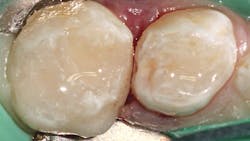

In this case, a W3 ivory rubber dam clamp is placed on tooth A to be restored with an intracoronal restoration. Adjacent tooth B will be restored with a prefabricated pediatric zirconia crown (NuSmile; figure 1). A Hedy rubber dam with a slot style is placed extending from tooth A to the mesial of tooth C.

The restorative material is warmed first in a Caps WarmerNano-ORMOCER materials provide clinicians with an excellent restorative option for pediatric patients that can appease concerned caregivers without disrupting current workflows. No doubt public scrutiny of our restorative materials will continue, whether their conclusions are legitimate or ill-informed. But we will also continue to see children with dental caries, so we would do well to add new materials to our armamentarium that can support good oral health outcomes and reassure caregivers of their safety.